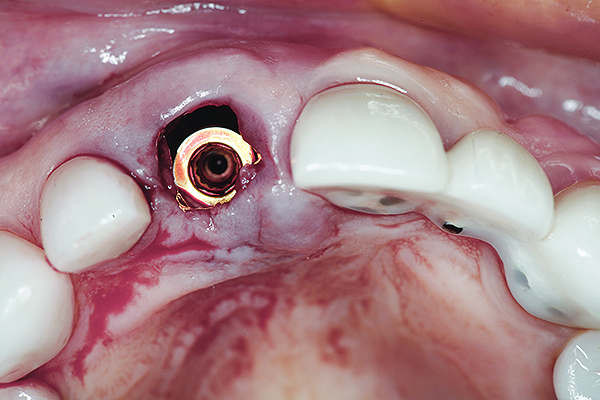

Fig 16. Try-in of the definitive titanium-nitride–coated abutment.

Figure 16